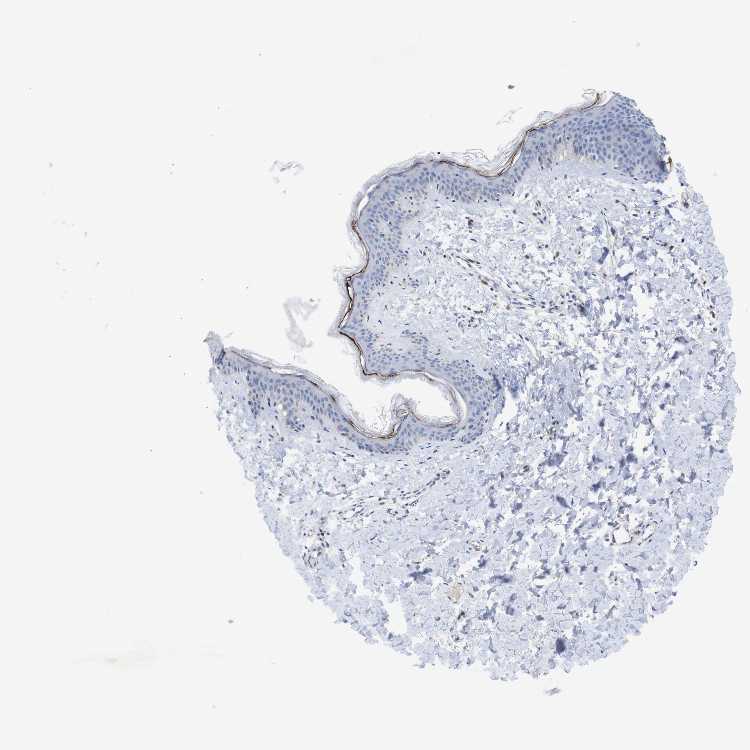

SKIN 1 - Antibody stainingi

Antibody staining in the annotated cell types in the current human tissue is reported as not detected, low, medium, or high, based on conventional immunohistochemistry profiling in selected tissues. This score is based on the combination of the staining intensity and fraction of stained cells.

Each image is clickable and will lead to virtual microscopy that enables deeper exploration of all samples and also displays staining intensity scores, fraction scores and subcellular localization as well as patient and tissue information for each sample.

Antibody HPA014520Antibody CAB002720

Langerhans Not detectedNot detected

Fibroblasts Not detectedNot detected

Keratinocytes Not detectedNot detected

Melanocytes LowNot detected